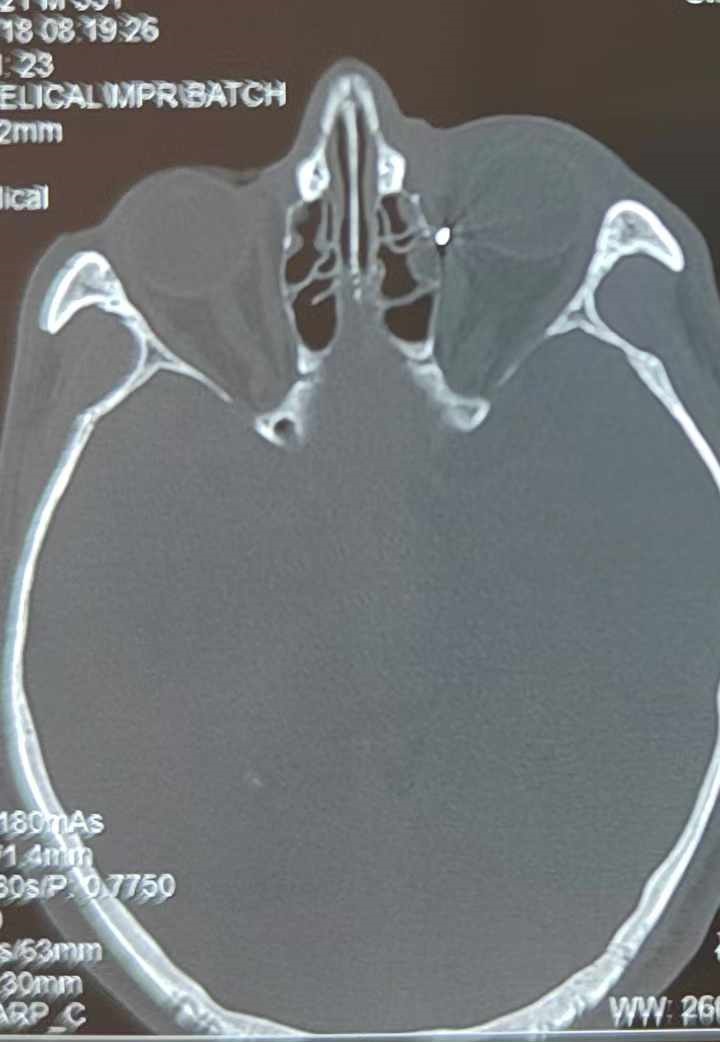

從CT報(bào)告中可以看出,高先生眼內(nèi)的異物不是很大,但位于眼窩深處,緊鄰鼻骨,從CT影像判斷應(yīng)該是金屬或合金異物。一般臨床上遇到這樣的情況,醫(yī)生會(huì)建議“保守觀察”,若異物傷及神經(jīng)、發(fā)生炎癥感染等,則需到條件較好、有眼眶病和眼外傷專業(yè)醫(yī)師的醫(yī)院進(jìn)行二期眶內(nèi)異物取出術(shù)(2021年《中國(guó)眼眶異物診斷和治療專家共識(shí)》)。

李海波博士介紹,眶內(nèi)異物想要通過(guò)手術(shù)取出,難度很大,一是因?yàn)槲恢秒[匿,無(wú)法實(shí)現(xiàn)可視化操作;二是如果是磁性異物,現(xiàn)有手術(shù)工具磁性強(qiáng)度有限,很難吸出這么深的異物;三是可操作空間極為狹小,眶周軟組織多,異物周邊包裹緊密,像高先生這種情況,異物周邊還有很多神經(jīng)、血管,手術(shù)難度更高。